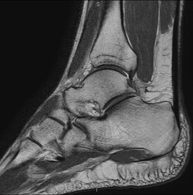

Exploración para el estudio de la articulación y sus frecuentes lesiones de ligamentos (esguinces) así como de la afectación de otras estructuras como el cartílago o el hueso. También es de gran utilidad para diagnosticar alteraciones en el tendón de Aquiles (tendinitis, roturas). Duración de aproximadamente 20 minutos. No emplea radiación ionizante. - RM Pie

- Artro-RM Tobillo

Exploración para el estudio de las lesiones en pequeñas estructuras anatómicas de la articulación que suelen lesionarse en pacientes que sufren luxación o inestabilidad crónica. El estudio viene precedido por una inyección de contraste en el interior de la articulación, realizada bajo control de rayos X. Duración global de los dos procedimientos es de 50 minutos.